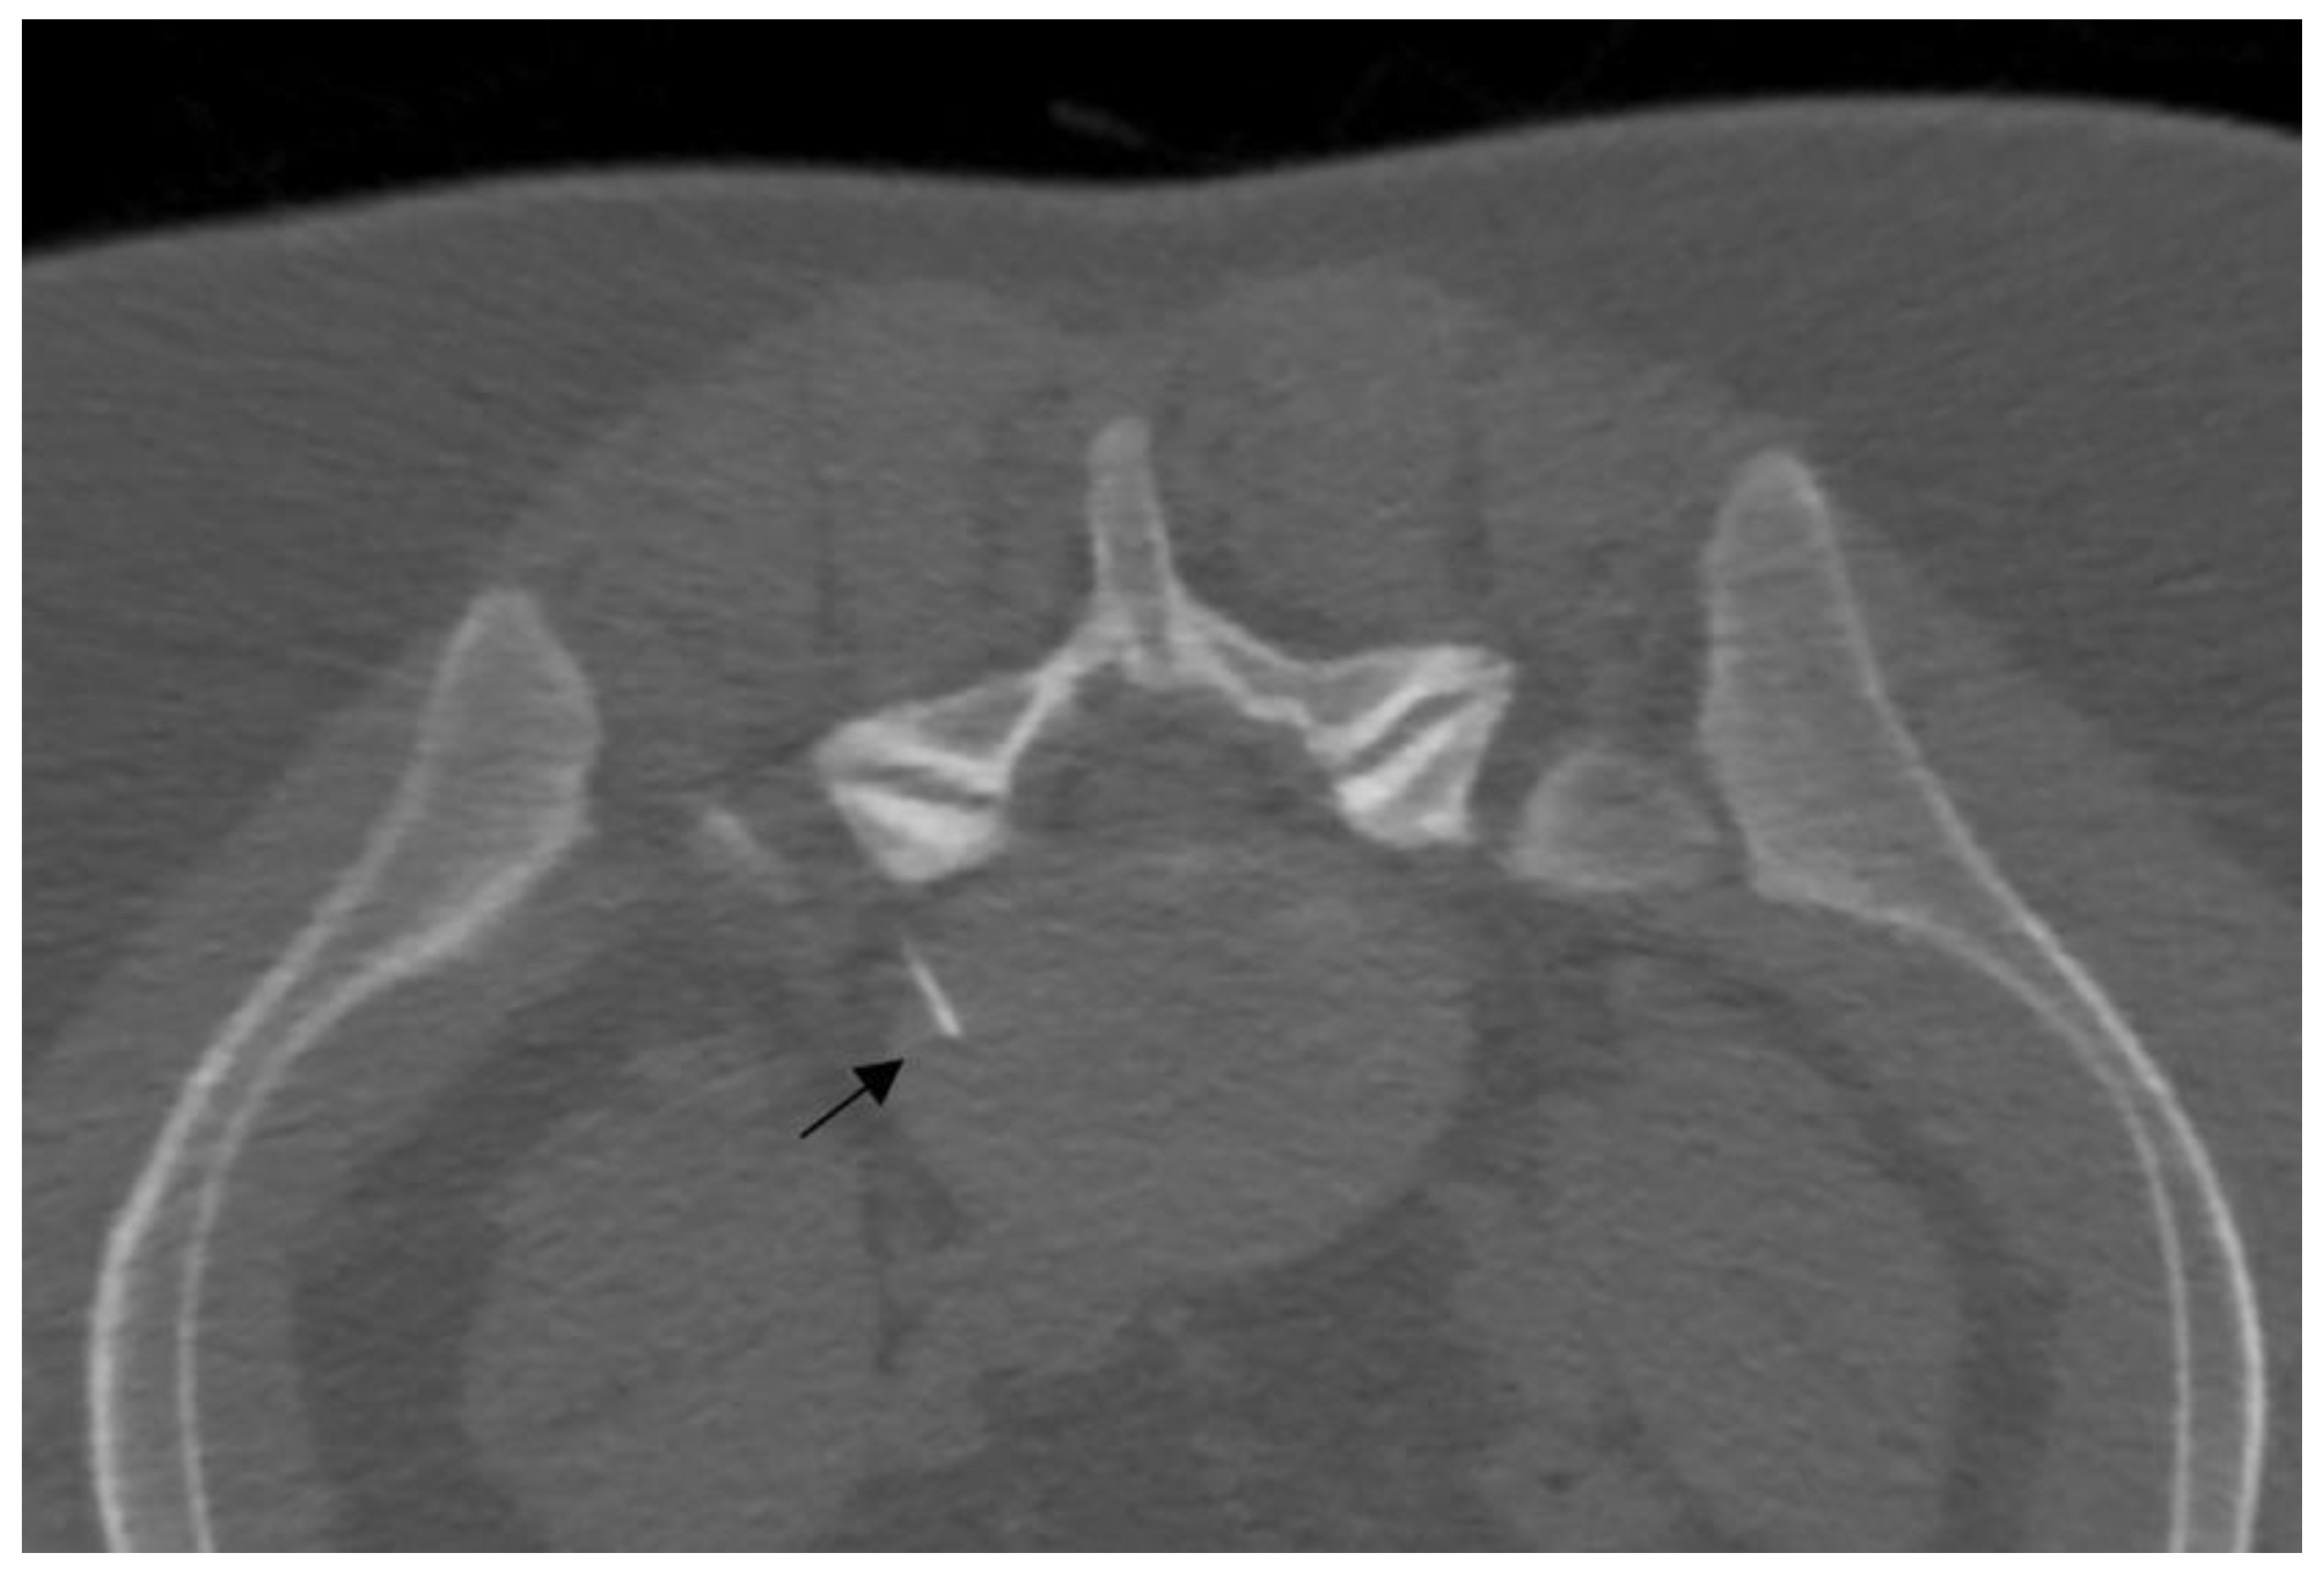

Figure 3.

A 25-year-old patient with L5 discogenic pain treated with ozone therapy; notice the tip of the needle is located in the lumbar disc (black arrow).